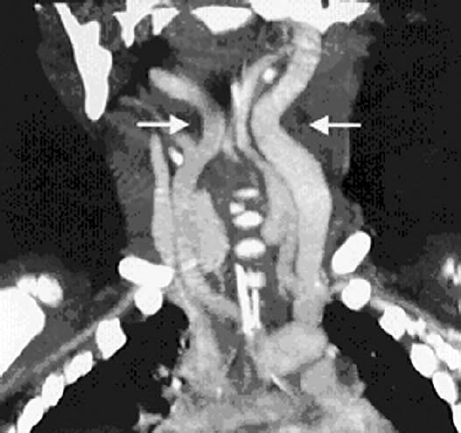

Although routine blood work is not indicated in otherwise healthy children, if there is concern for bleeding disorders or platelet dysfunction, appropriate laboratory work and correction of bleeding abnormalities should be completed prior to undergoing VPI surgery. Several studies cite younger age as a possible risk factor for perioperative complications. Fraulin et al. found that patients who developed airway obstruction after PF were younger than patients who did not develop this complication (7.8 years versus 9.3 years).4 In a retrospective review of SP, all cases of prolonged airway compromise occurred in patients 5 years old or younger.5 However, it is has been shown that SP can be performed safely in children as young as 3 years of age.11 Consideration should be given to assessing the position of the internal carotid arteries in patients with DiGeorge or velocardiofacial syndromes ( Fig. 14.1 ).